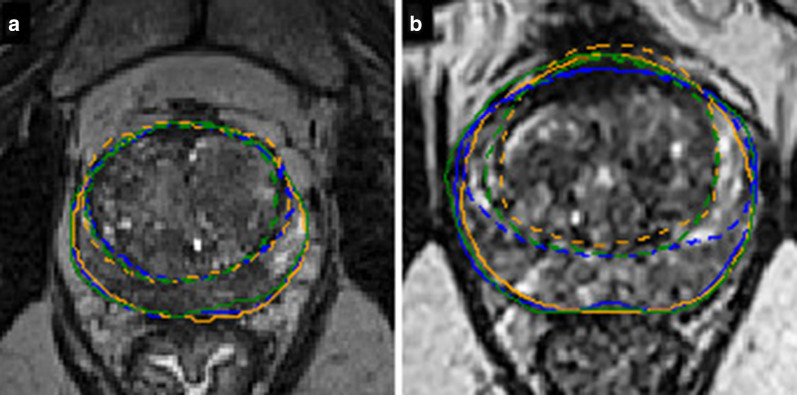

Fig. 2.

Examples of low (a) and high (b) segmentation variabilities for WG (full line) and TZ (dashed line) on a transverse slice for one rater of each group of experience (blue for expert, orange for senior, green for resident)

Concerning the TZ we found a higher variability with a mean DSC of 0.88 (± SD = 0.05), an increase of the mean HD to 12.0 (± 4.9) voxels, and an increase of the mean AHD to 0.31 (± 0.19) voxels. An example of segmentation variability between the different readers groups is shown in Fig. 2, and the global results are illustrated in Fig. 3.